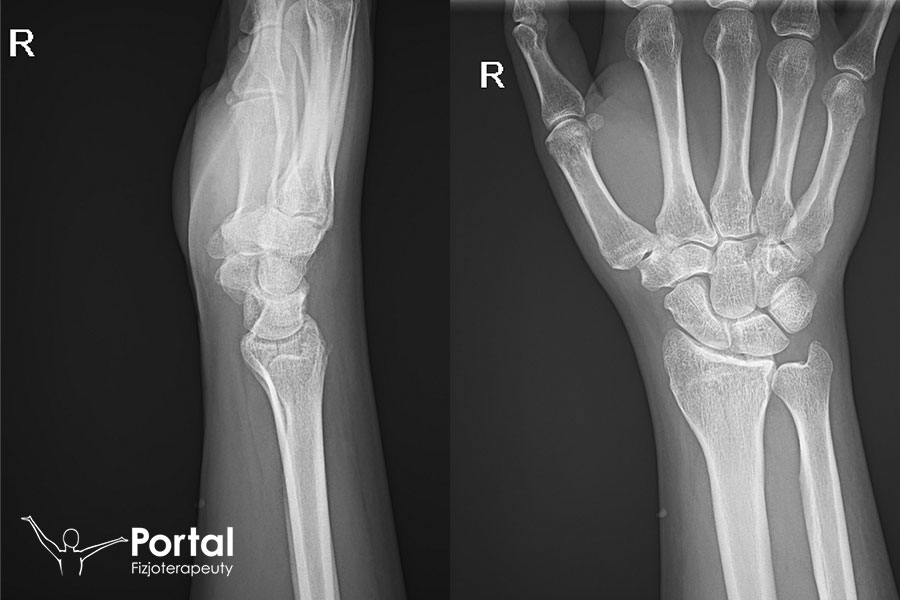

Kolana szpotawe to wada postawy, w której oś podudzia tworzy z osią uda kąt otwarty do wewnątrz. Odległość między kolanami w staniu ze złączonymi kostkami przyśrodkowymi wynosi powyżej 4 cm. Wada ta nasila się w okresie rozwoju i wzrostu organizmu (wiek szkolny). Przyjmuje się, że ma swój początek pomiędzy 1 a 3 rokiem życia. Jest wówczas zjawiskiem fizjologicznym, które zanika około 4 roku życia. Zwykle dotyczy obu kończyn dolnych. Wada obejmująca wyłącznie jedną kończynę dolną jest wskazaniem do badania radiologicznego.

Inną przyczyną może być przebyte zapalenie kości, choroba Blounta lub doznany uraz. Warto także prześledzić choroby występujące w rodzinie.